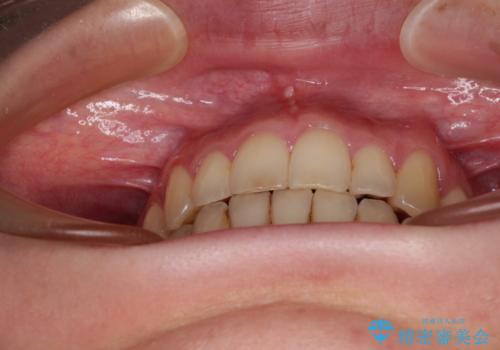

- 上下前歯の隙間を気にして来院された患者様です。

下顎前歯が1本欠損しており、上下小臼歯はクロスバイトとなり、上下前歯の接触もないという不正咬合の状態でした。

クロスバイトはワイヤー矯正が得意とするところであり、上下前歯の非接触や開咬はインビザラインの得意とするところであるので、ワイヤー装置により事前にクロスバイトを改善し、その後にインビザラインにて仕上げていくこととしました。

奥歯の咬み合わせに問題がある場合、インビザラインでは改善できないことが多々あります。事前にワイヤー装置により問題点を解消しておくことで、スムーズにインビザラインでの矯正治療を進めていくことができます。